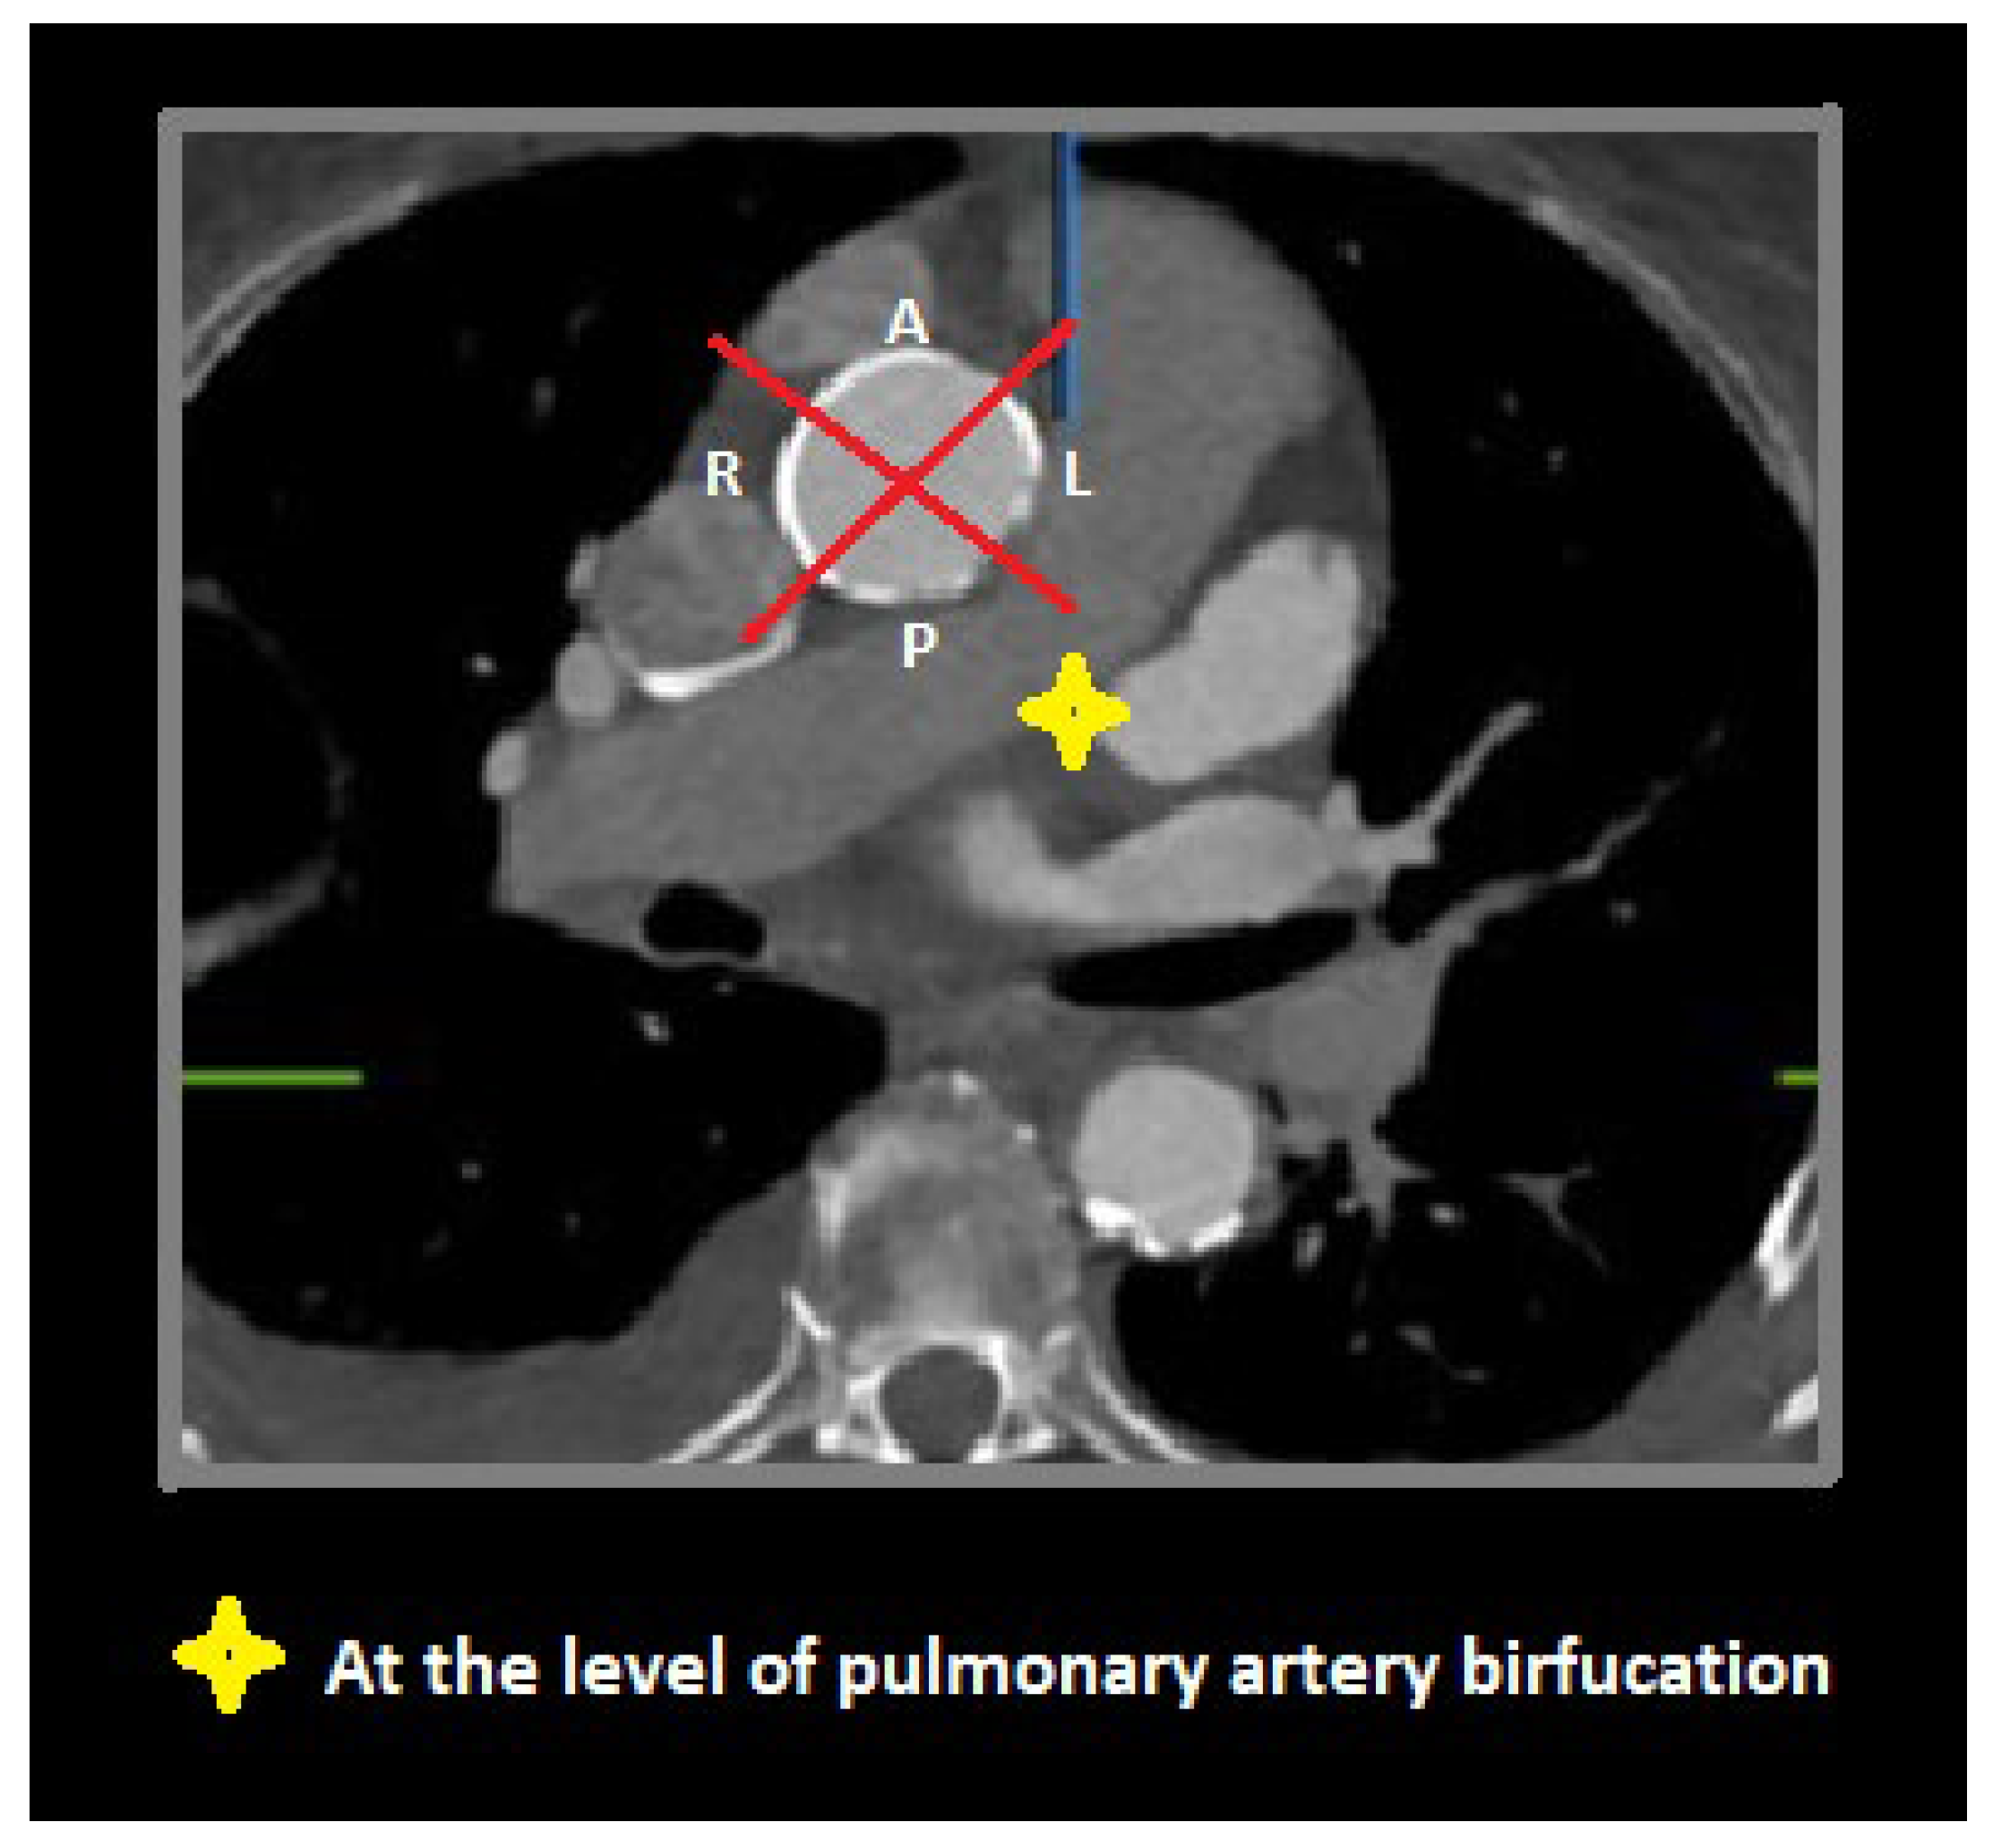

- (1)

- Proximal segment, from sinotubular junction to mid-ascending aorta (at level of pulmonary artery bifurcation);

- (2)

- Middle segment, from mid-ascending aorta (at pulmonary artery bifurcation) to origin of brachiocephalic trunk;

- (3)

- Distal segment, from origin of brachiocephalic trunk to origin of left subclavian artery.